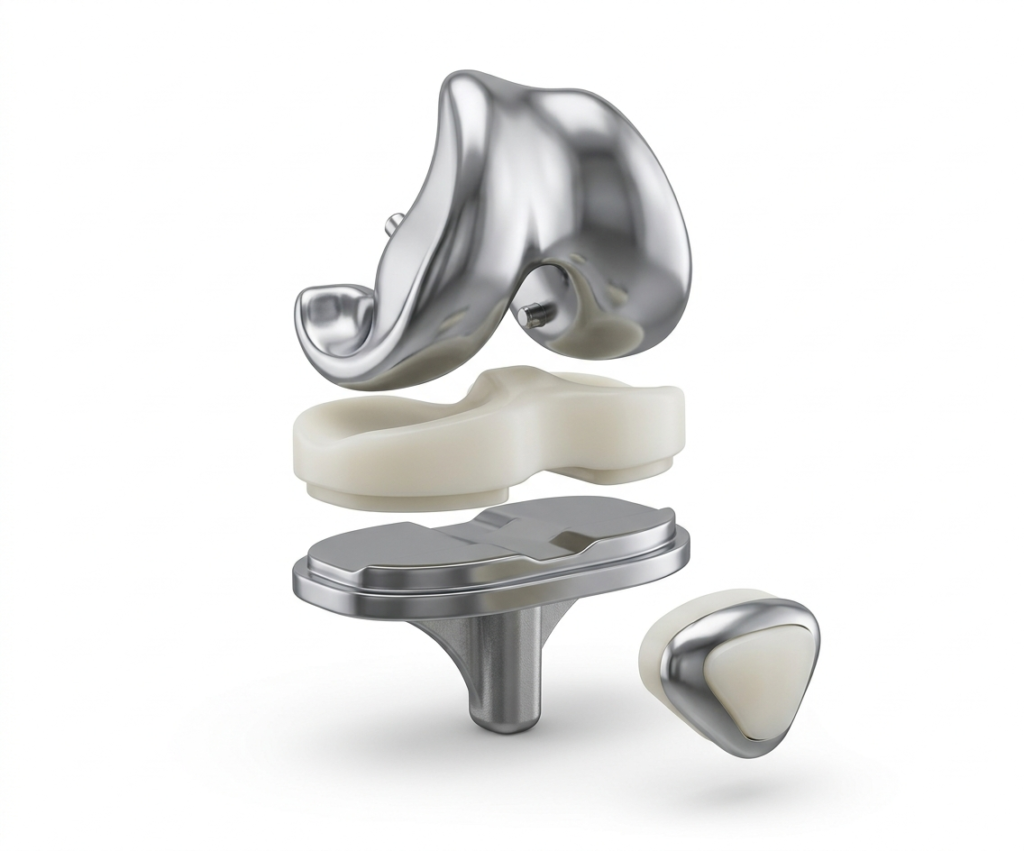

El reemplazo total de rodilla, también conocido como artroplastia de rodilla, es un procedimiento quirúrgico en el que las superficies articulares dañadas de la rodilla se retiran y se sustituyen por componentes artificiales de metal y polietileno de alta resistencia. Esta cirugía está diseñada para eliminar el dolor crónico debilitante y restaurar la función normal de la articulación.

1. Reemplazo Total de Rodilla

Se reemplazan por completo las tres superficies articulares: el extremo del fémur, la meseta tibial y la rótula. Es la opción más frecuente cuando toda la articulación presenta daño severo.

| 04 | Implantación de la prótesis Los componentes protésicos de metal (cromo-cobalto o titanio) y polietileno se fijan al hueso, replicando la biomecánica natural de la rodilla. |